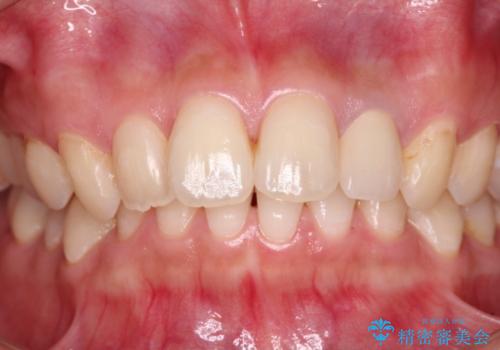

歯肉移植により歯肉ラインや歯の形態を整えることができ、ブリッジによる補綴としたことで舞えば全体の色調を整えることができました。